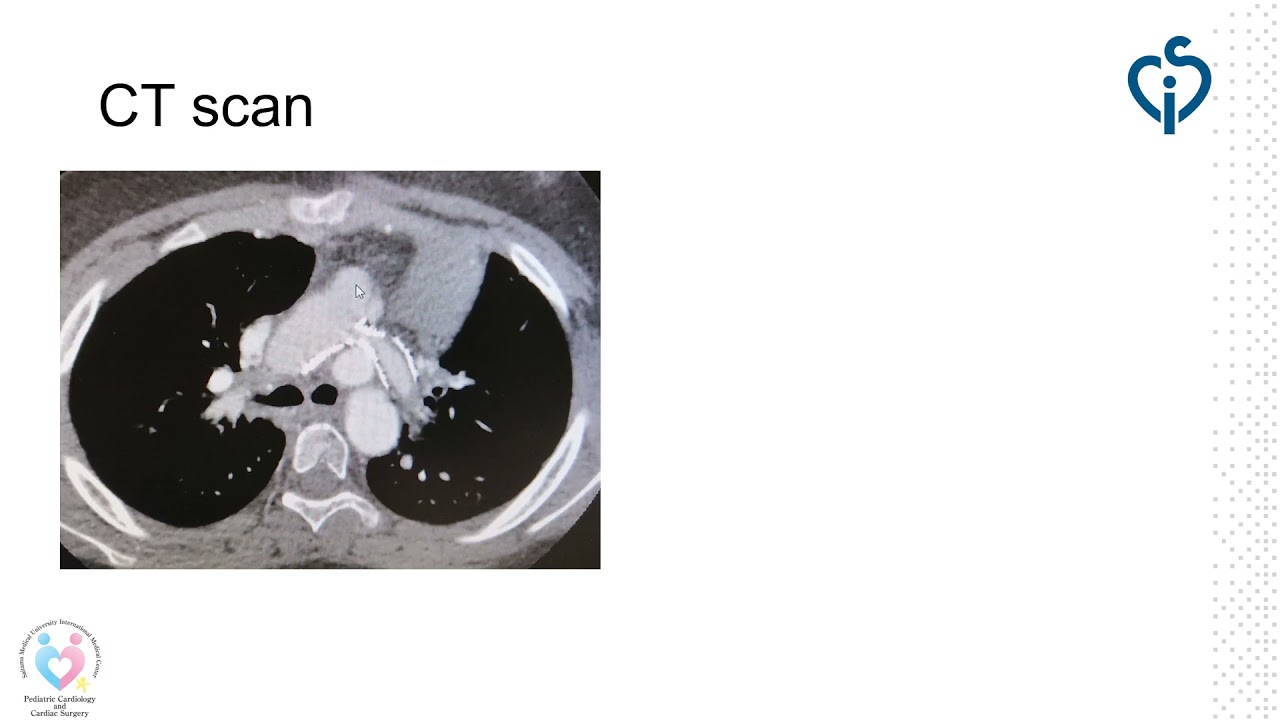

How should you treat coarctation and aortic stenosis in an adult with very high surgical risk?

By: Luis Fernandez Gonzalez, Hospital Universitario de Cruces, Baracaldo, Spain